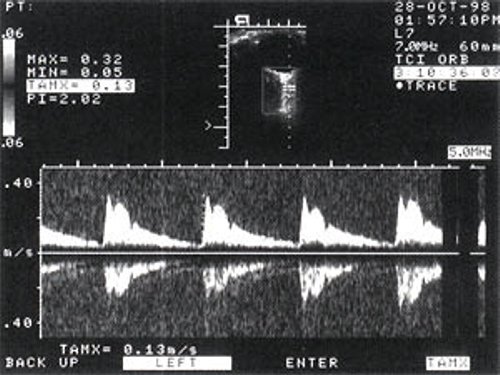

У всех пациентов выявляли глазничную артерию с носовой стороны от зрительного нерва после его пересечения, средний диаметр которой составил 1,5-2,0 мм. Кривая допплеровского спектра сдвига частот в глазной артерии характеризовалась высоким систолическим пиком с хорошо выраженной инцизурой и систолической составляющей - двухфазный поток (рис. 2, 3). Визуализация задних коротких цилиарных артерий вызывала некоторые затруднения, связанные с условием проведения исследования на подвижном объекте. Однако и от них при наличии достаточного практического опыта можно всегда получить четкий спектр допплеровской кривой (рис. 4, 5). Особенностью спектра было отсутствие инцизуры - монофазный поток.

Рис. 3. Дуплексное сканирование кровотока задней короткой цилиарной артерии в норме.

Рис. 5. Дуплексное сканирование кровотока задней короткой цилиарной артерии при глаукоме.